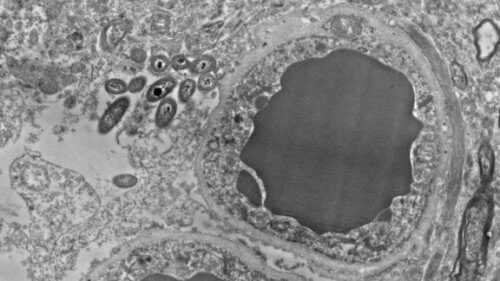

Wspomniana bariera składa się między innymi z komórek glejowych, które wraz z neuronami chronią mózg przez neurotoksynami i innymi niebezpiecznymi substancjami. Te niebezpieczne związki mogą jednak w pewnych okolicznościach przedostać się do mózgu i prowadzić do poważnych, nawet śmiertelnych chorób. Najciekawsze jest to, że astrocyty, czyli największe z chroniących mózg komórek glejowych, zdają się być ulubionym miejscem bytowania bakterii jelitowych.